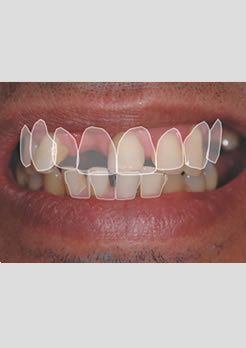

Prótese fixa instalada dois dias após a colocação dos implantes

Antes e depois do tratamento

Novo perfil rejuvenecido